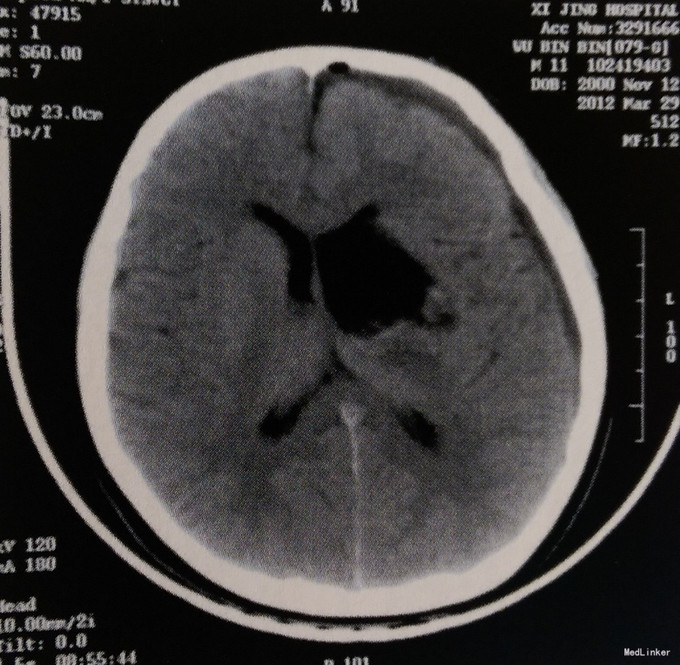

患者,男,11岁。主因头痛2周、意识障碍2天入院。 患者2周前出现持续性头胀痛,1周前出现呕吐,入食即吐,2天前昏迷。在当地医院行头颅CT检查:颅内肿瘤。遂来我院急诊中心就诊,给予“脱水、营养神经、对症处理”,随即急诊以“左侧基底节区及丘脑肿瘤”收入我科。既往体健,无其他相关病史。

体格检查:意识呈昏睡状,查体不配合,双侧瞳孔等大等圆、对光反射迟钝,四肢肌力III级,肌张力轻度增高,右侧Babinski征阳性,颈抵抗阳性。 头颅MRI检查:左侧基底节区及丘脑占位性病变,呈囊实性混杂成分,边界欠清,实性成分呈明显不均匀强化,考虑生殖细胞瘤或胶质瘤可能性大;左侧侧脑室明显受压变形,中线向右侧移位;幕上梗阻性脑积水。

诊断:左侧基底节区及丘脑肿瘤 治疗:患者在命麻下行“开颅左侧基底节区及丘脑瘤切除术”。

术后一周行CT检查:左侧基底节区及丘脑肿瘤完全切除,术区软化灶形成,左侧侧脑室形状及中线结构基本恢复正常,左额顶部少量硬膜下积液。